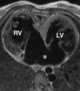

Mesocardia